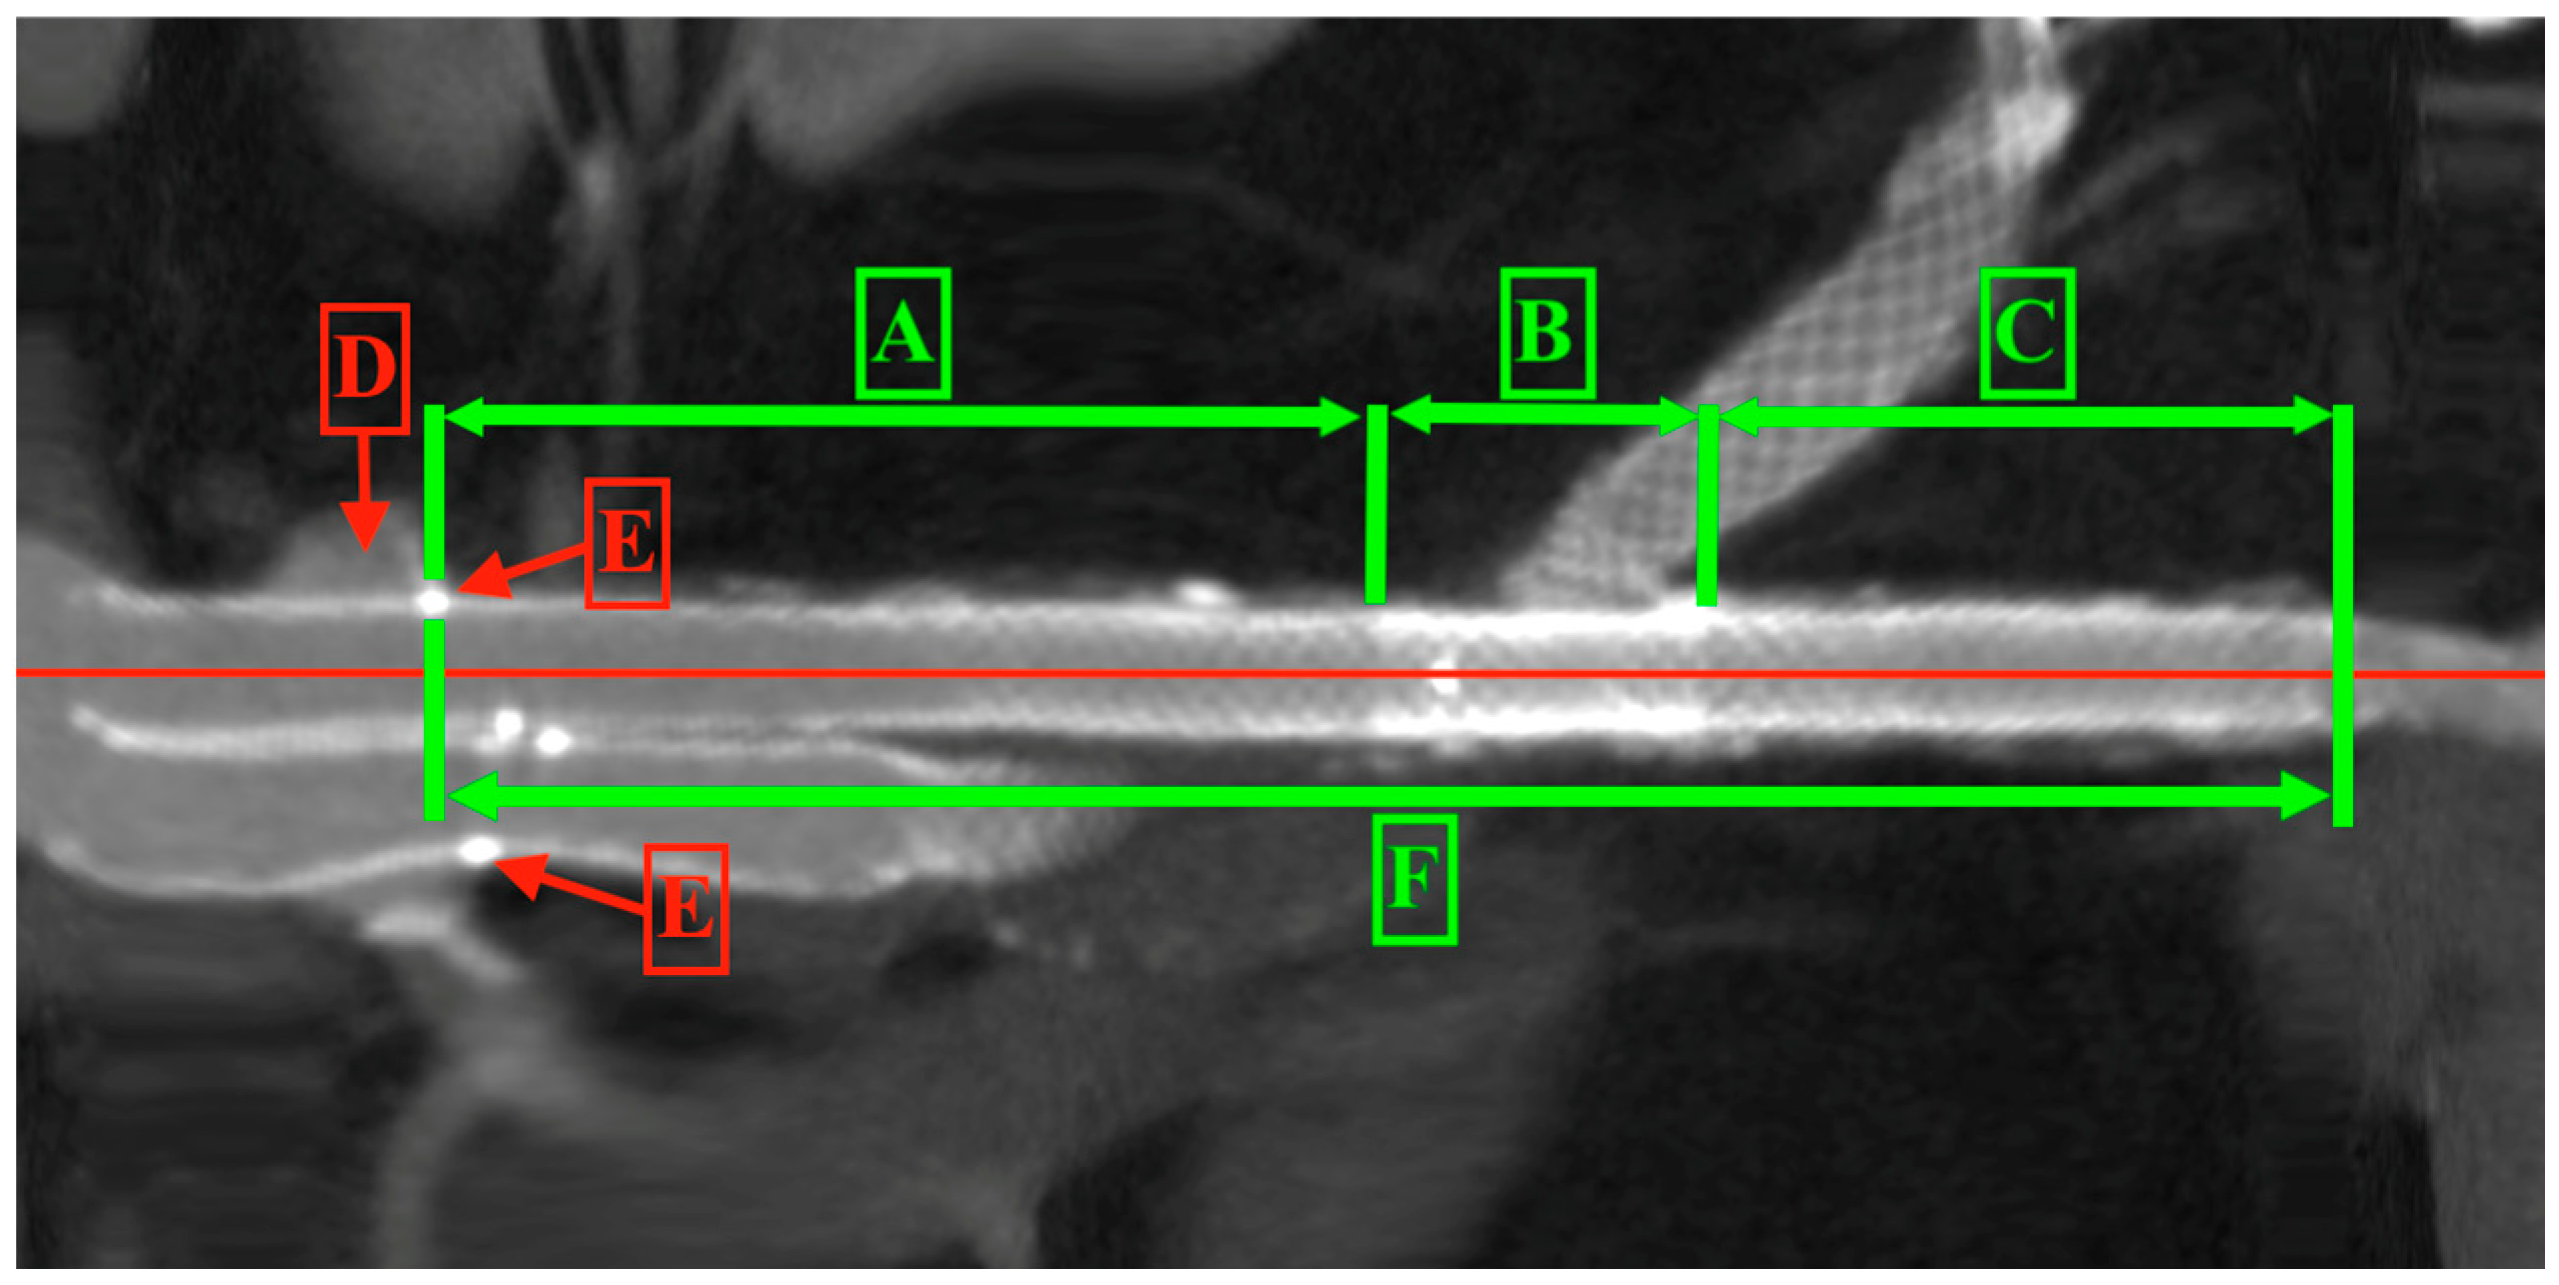

Measurements included the total length of the stent graft defined as the segments A and B, the length of the proximal part of the D-shaped stent graft, the aortic stent graft, the overlapping zone, the iliac stent graft defined as the segments B and C, and the distal part of the iliac extension (Figure 5).

Figure 5. ALTURA™ stent graft parts and segments. A—proximal part of aortic stent graft, B—overlapping zone of aortic stent graft and iliac extension, A and B—aortic stent graft, C—distal part of iliac extension, B and C—iliac extension, D—renal artery, E—renal artery radiopaque marker, F—total length of stent graft. The red line is the central line of the stent graft and artery.